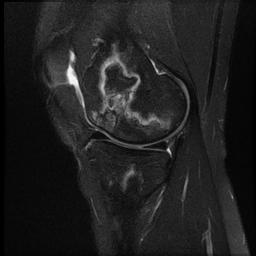

Staging Insall

Stage 1

- normal x-ray with positive bone scan / MRI

Stage 2

- subtle flattening of weight bearing portion of condyle

Stage 3

- typical lesion

- radiolucent area with sclerotic halo

Stage 4

- halo thickened with subchondral collapse

Stage 5

- degenerative change

- varus or valgus angulation